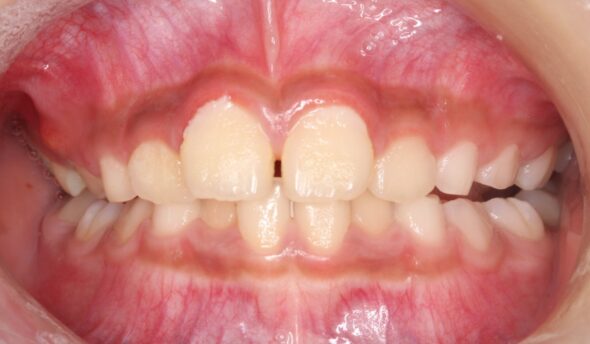

2026/03/17全体的な歯並びのがたつきが気になる9歳女児の矯正症例紹介 今回ご紹介する患者様は、全体的な歯並びのがたつきを気にされており、矯正検査後叢生Ⅰ級と診断いたしました。 治療前後の比較 矯正術前:正面 矯正術後:正面 矯正術前:右側 矯正術後:右側 矯正術前:左側 矯正術後:左側 矯正術前:上顎 矯正術後:上顎 矯正術前:下顎 矯正術後:下顎 矯正術前:前歯部あおり 矯正術後:前歯部あおり 矯正術前:オーバージェット 矯正術後:オーバージェット 主訴 全体的な歯並びのがたつきが気になる 治療期間 ・マウスピース矯正:3カ月 治療費用 66…